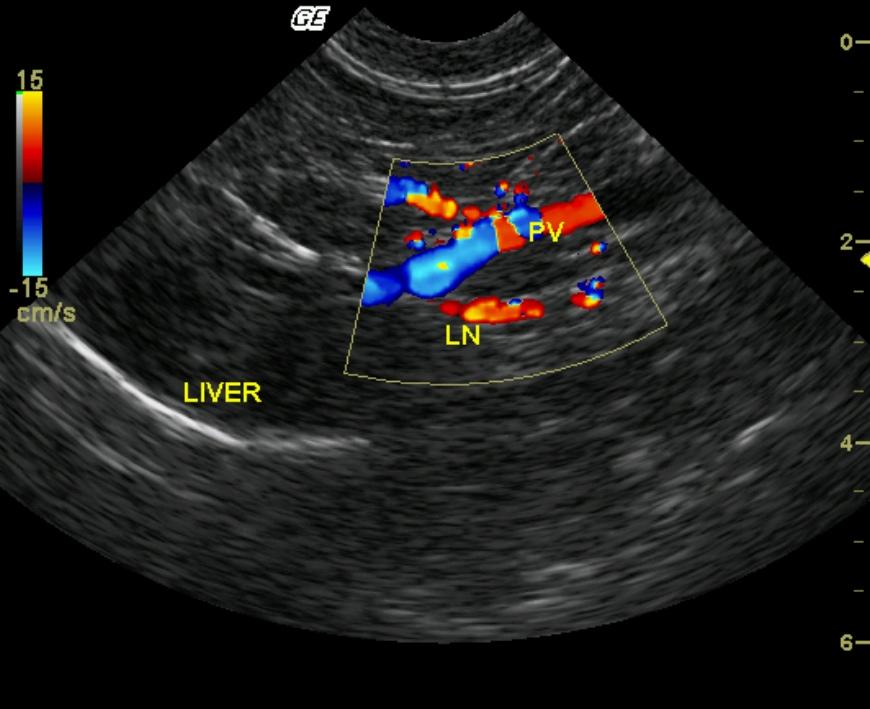

A 7-year-old F intact DSH was presented for the evaluation of dyspnea. The physical exam revealed muffled heart sounds and a thoracocentesis was performed bilaterally. One hundred milliliters (ml) of fluid was obtained from the right hemithorax and 35 ml from the left. Fluid analysis revealed cellularity to be moderate to high and RBC 100,000. Blood chemistry was performed and revealed the following abnormalities: CK 1359, albumin 3.4 g/l, direct bilirubin 0.2, and glucose 158 mg/dl.